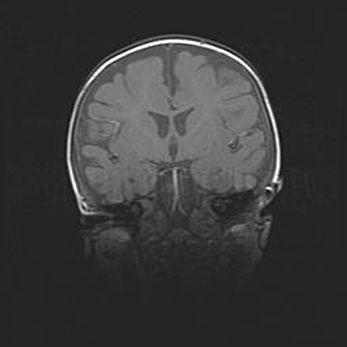

Открытая гидроцефалия.

Возраст: 9 месяцев 12 дней

Вес: 6800 г

Пол: мужской

Окружность головы: 41,5 см

Срок гестации: 28 недель

Гидроцефалия головного мозга у новорожденных имеет характерный признак: опережающий рост окружности головы приводит к визуально хорошо определяемой гидроцефальной форме сильно увеличенного в объёме черепа. Детские неврологи определяют следующие симптомы гидроцефалии у грудничков: выбухающий напряжённый родничок, частое запрокидывание головы, смещение глазных яблок к низу.